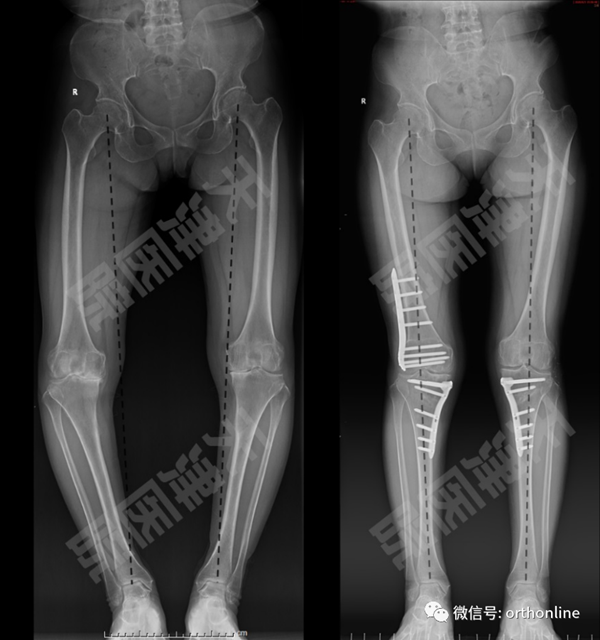

马教授讲了这么一个病例。两年前,一位50岁双膝严重内翻畸形女性患者,对于此类畸形患者,是进行关节置换还是截骨保膝手术?马信龙教授团队通过低剂量CT重建及影像资料分析,患者膝关节外侧间室完好,且考虑到患者年龄及运动量需求决定通过截骨矫形恢复下肢力线,纠正内翻畸形。

为此,在术前影像上分析畸形来源,决定行右侧股骨外侧闭合+胫骨内侧撑开截骨,及左侧胫骨内侧撑开截骨。在术前经过数字技术反复模拟设计个性化手术方案,为了术中精准截骨矫形,专门设计了截骨矫形导向器分别完成股骨及胫骨的截骨、矫形。为应对双侧胫骨撑开截骨留下的骨缺损,分别设计髂骨导板,切取三皮质髂骨块完美填充骨缺损。术前通过3D打印技术等比例打印骨骼及导向器模型,并进行模拟手术。术中在截骨矫形导向器的辅助下完成精准截骨矫形,术后患者下肢畸形得到纠正,力线位置与预期相符,内侧间室恢复良好,保留了患者的自然关节,最大程度上保护了膝关节的功能。